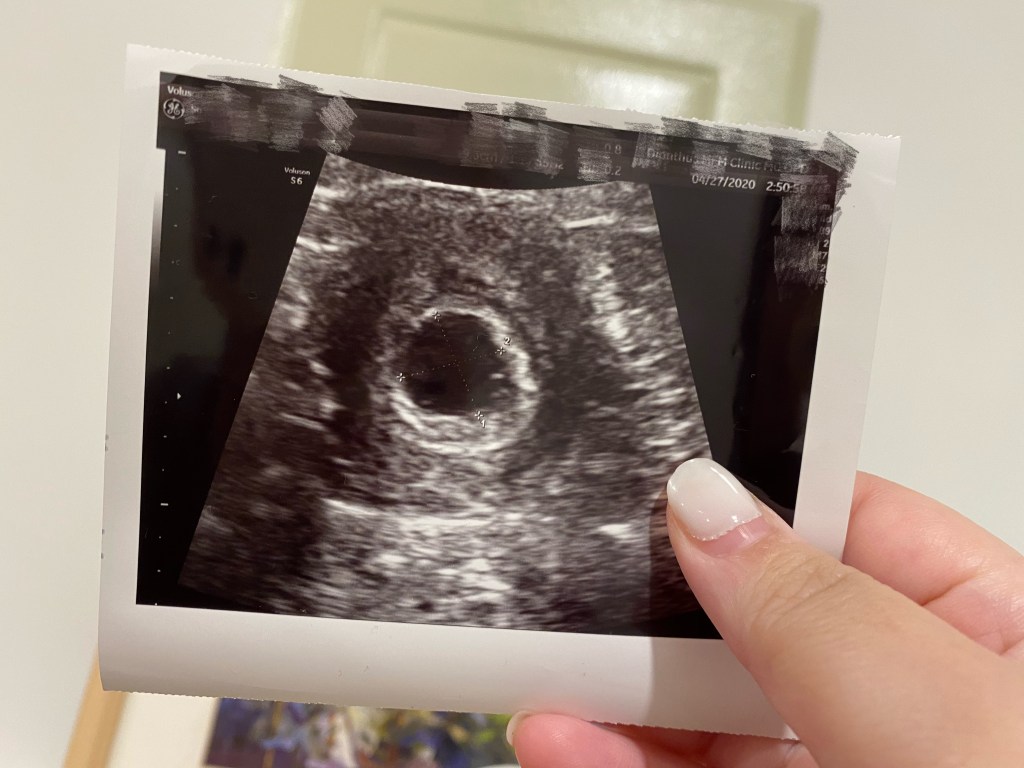

懷蛋黃那次,我大概五週就前往婦產科檢查,這次想說都是二寶了,就淡定一點,反正太早去也只是確定受精卵有沒有乖乖地落在子宮內,那還不如晚一點,搞不好可以一起看到心跳。於是我預約了大概六週左右的時間去產檢。不過這次我還是只有確定胎囊有在子宮內,還暫時看不到心跳,於是預約了兩週後回診。

第8週左右的產檢時,我們看到、也聽到了二寶的心跳。薑再老好像還是不會辣,因為我聽了還是好感動、眼淚又快奪框而出,因為我知道寶寶目前一切都好。